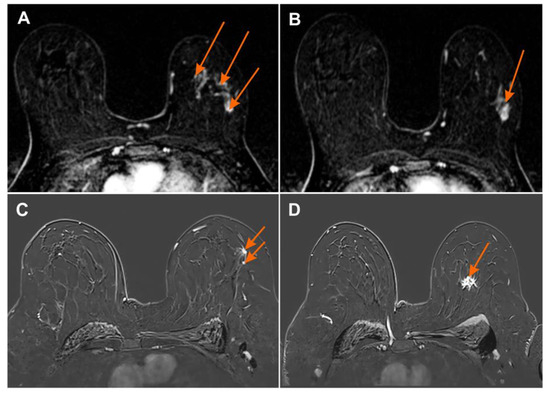

Figure 4. Magnetic resonance imaging (MRI) subtraction image (A,B) 2 min after contrast injection irregular mass with heterogeneous enhancement BI-RADS 6 with numerous foci of contrast uptake showing multicentric cancer BI-RADS 4 (orange arrows); (C,D) MRI subtraction image 2 min after contrast injection irregular mass with heterogeneous enhancement BI-RADS 6 with additional foci of contrast uptake showing multicentric cancer BI-RADS 4 (orange arrows).